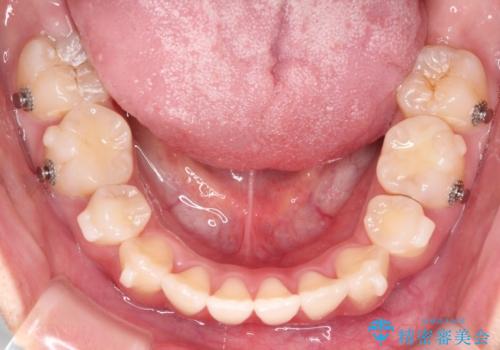

【インビザライン】シザーズバイト、抜歯矯正

- インビザライン

- オープンバイトを主訴に来院された患者様です。

抜歯を行うことで、インビザラインを用いて前歯を下げることができ、同時にオープンバイトを改善することができました。

今回はインビザラインのみで治療を終了することができました。